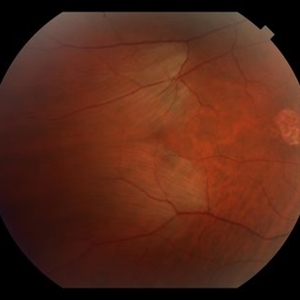

POHS-CNVM

Jan 7 2018 by John S. King, MD

17-year-old hx scotoma a year ago; 1-2 months of worsening scotoma; small chorio-retinal punched out lesions in mid-periph; midperipheral curvilinear pigment band in inf 180 degrees; staining and leakage on FA; avastin administered.

Imaging device: Topcon

Condition/keywords: choroidal neovascular membrane (CNVM), presumed ocular histoplasmosis syndrome (POHS)

OHS-CNVM

17-year-old hx scotoma a year ago; 1-2 months of worsening scotoma; small cr punched out lesions in mid-periph; midperipheral curvilinear pigment band in inf 180 degrees.

Condition/keywords: choroidal neovascular membrane (CNVM), ocular histoplasmosis syndrome (OHS)